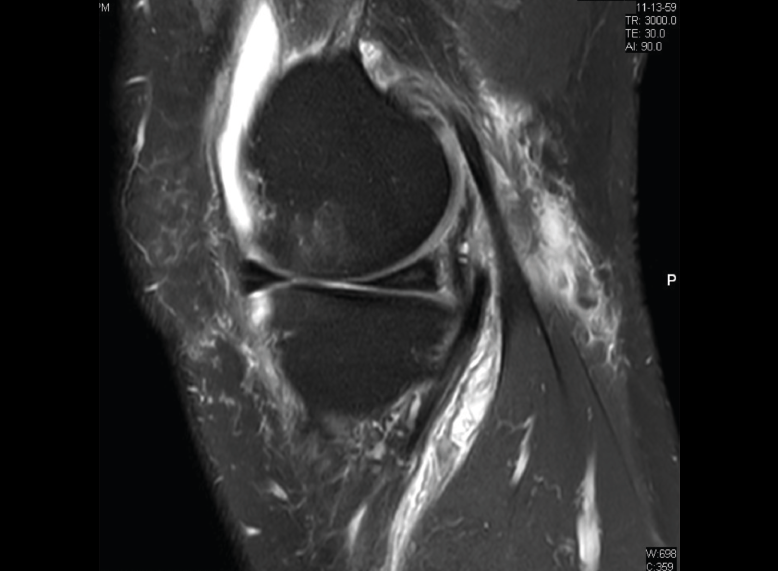

Figura 30. Corte de secuencia sagital T2 Fat-Sat de resonancia magnética de rodilla: menisco externo normal.

Se identifican como estructuras hipointensas en todas las secuencias, con asta anterior y posterior de morfología triangular.

Figura 31. Corte de secuencia sagital T2 Fat-Sat de resonancia magnética de rodilla: menisco interno normal.

La RM es la técnica de elección en el diagnóstico de la patología meniscal(17)(Figuras 30, 31, 32, 33, 34 y 35).